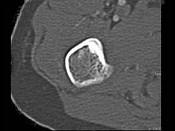

问题 男,28岁,右上肢疼痛,夜间加重,服用止痛药可缓解,结合图像,最可能的诊断是?(?)

选项 A.骨瘤 B.骨软骨瘤 C.骨样骨瘤 D.骨囊肿 E.成骨细胞瘤

答案 C